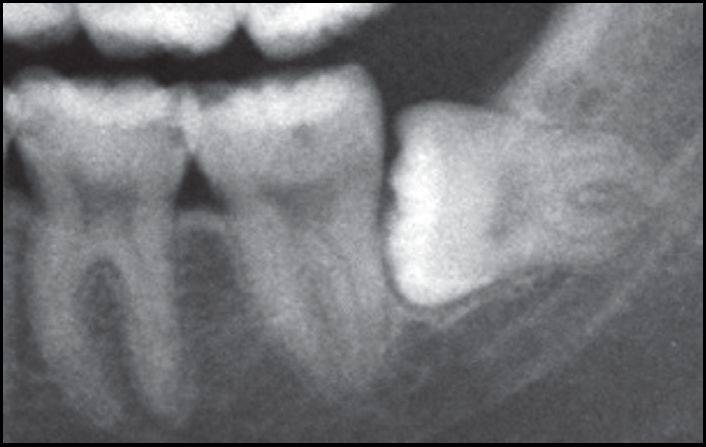

B.X线显示阻生智齿水平中位